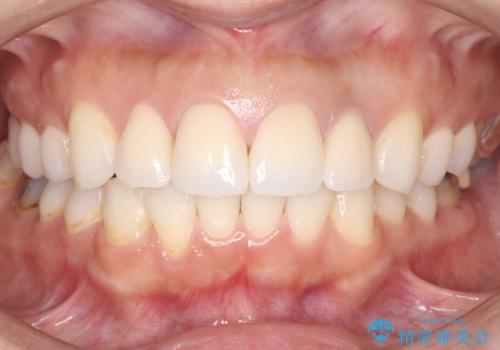

前歯の突出を防ぎながらガタつきを解消。上下左右4番抜歯による審美ワイヤー矯正

前歯の突出と下顎の偏位を改善。審美ワイヤーで整えるバランスの良い歯並び